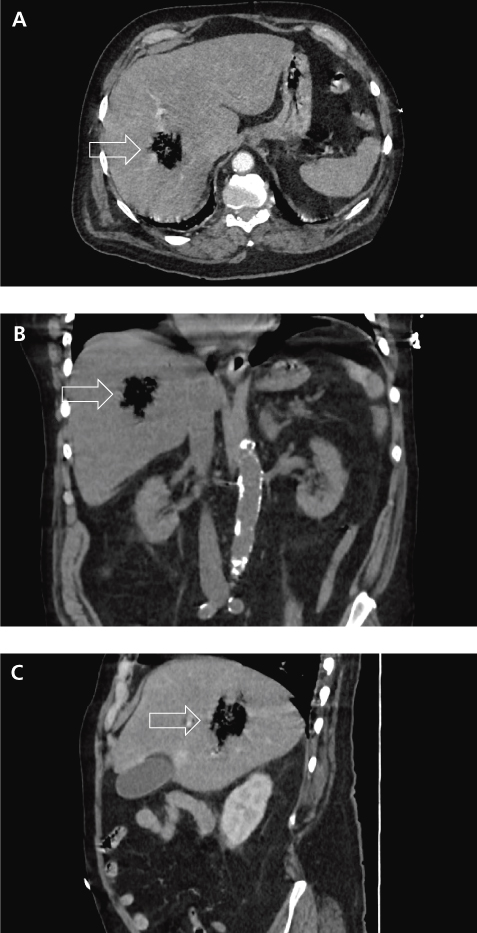

IntroductionNous rapportons le diagnostic et la prise en charge d’un cas d’hépatite emphysémateuse. Cette maladie est une infection rare et sévère du foie avec moins de 20 cas décrits dans la littérature. Le scanner abdomino- pelvien réalisé en raison d’un ictère et de douleurs abdominales avec sepsis sévère a montré une image aérique irrégulière hépatique du segment VII. Les hémocultures étaient positives à Klebsiella pneumoniae et Clostridium perfringens. Le patient est décédé quelques heures après [...]